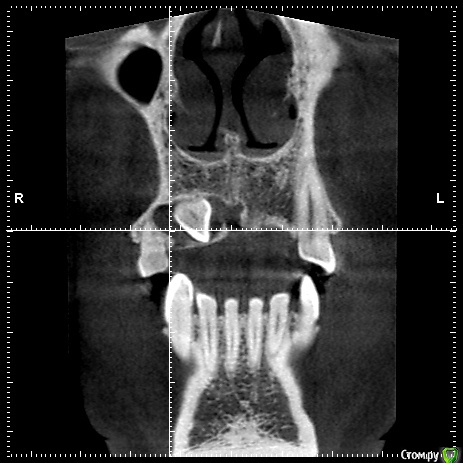

natalie_summerwhile Опубликовано 10 июля, 2017 Автор Поделиться Опубликовано 10 июля, 2017 Во рту вместо клыка молочный Ссылка на комментарий